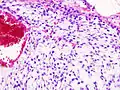

Histopathologic image of chondrosarcoma of the chest wall. Surgical resection of recurrent mass. H & E stain.